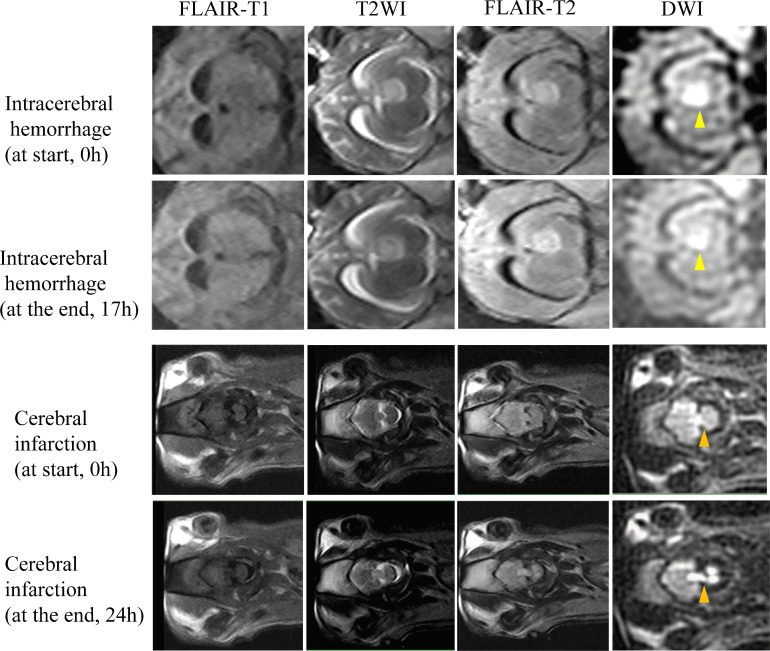

Methods: A novel HEIR sequence based on fluid-attenuated inversion recovery T1-weighted, with a scanning time of 1 min and 17 s, was developed using an ICH and AIS pig model on a 0.23-T MRI. Images of the pig model were obtained hourly for 24 hours in order to monitor value changes on T1/T2 and verify the differential diagnosis of AIS and ICH. Then, 30 patients with AIS and 30 patients with ICH with confirmed diagnoses by 3T-MRI/CT were included. Diagnostic criteria on a 0.23-T MRI for ICH was the hyperintensity signal on both the diffusion-weighted imaging (DWI) and HEIR sequence, while for AIS was the hyperintensity on DWI and isointensity on the HEIR sequence. Two blinded raters independently assessed the images obtained by the 0.23-T MRI for the presence of ICH/AIS.

Results: In the pig model, setting the inversion time to 800 ms enabled clear differentiation of ICH from brain parenchymal tissue and AIS. In real patients, a correct 0.23-T MRI diagnosis of either an AIS or ICH was made in all 60 patients within 24 hours of symptom onset (100% overall accuracy). No adverse events occurred.